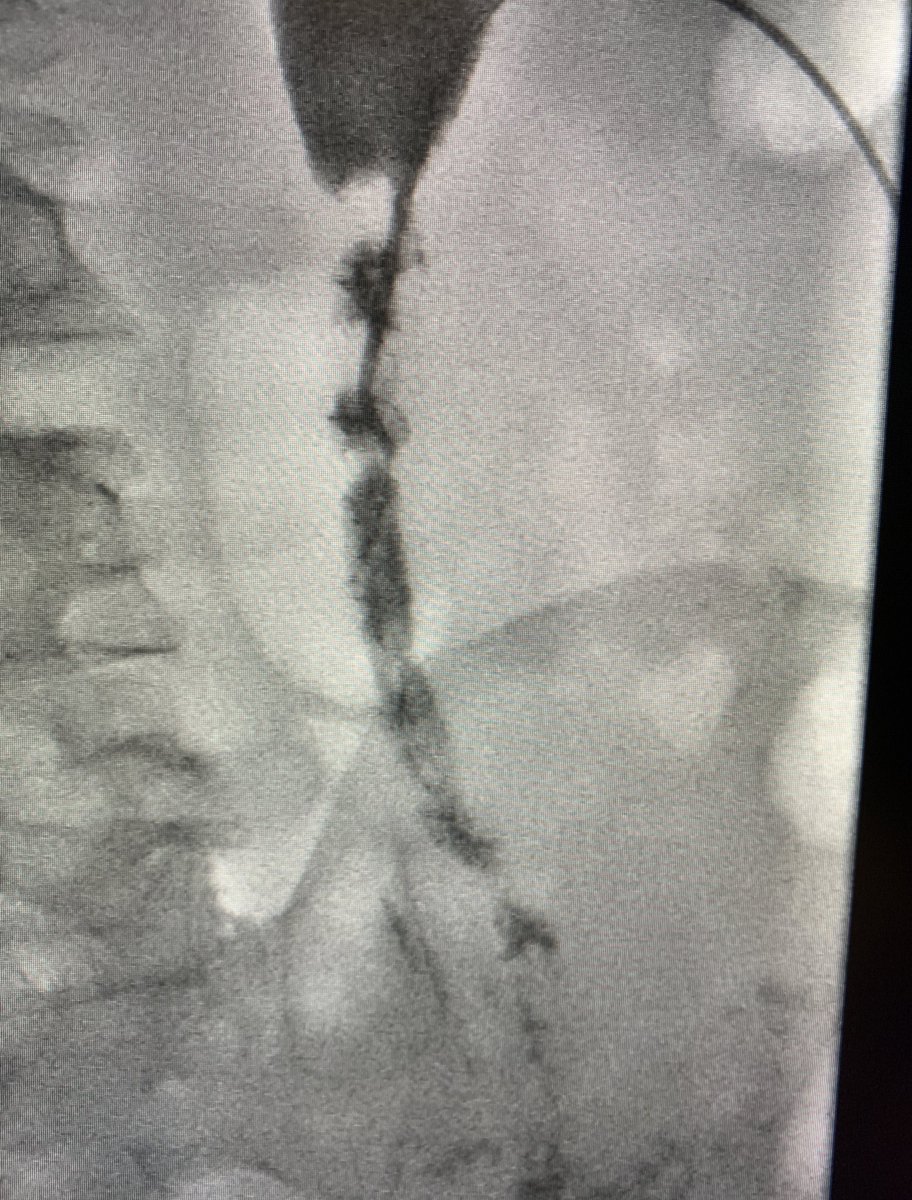

لأول مرة في المملكة، نجح #التخصصي في علاج عدد من المرضى الذين يعانون من انسداد وتضيق الشرايين الطرفية تحت الركبة، باستخدام تقنية مبتكرة تعتمد على إدخال دعامة حديثة تلقائية التحلل عبر قسطرة دقيقة في الفخذ، دون الحاجة إلى جراحة مفتوحة مما أسهم في استعادة تدفق الدم، وتخفيف الألم، وتسريع التئام الجروح، والحد من خطر البتر.